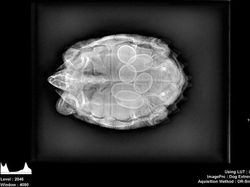

Penampakan dalam tubuh penyu saat hamil. (Foto: Brightside)